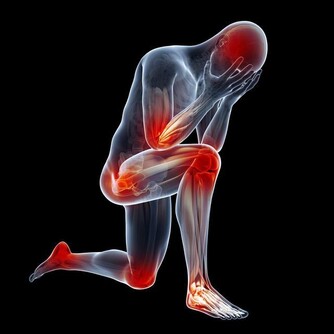

5. 脊髓型:是頸椎間盤突出或者骨贅壓迫到了脊髓,常見症狀有上下肢無力感,逐漸出現走路踩棉花感,步態拙笨甚至跌倒。後期還可出現排二便障礙。